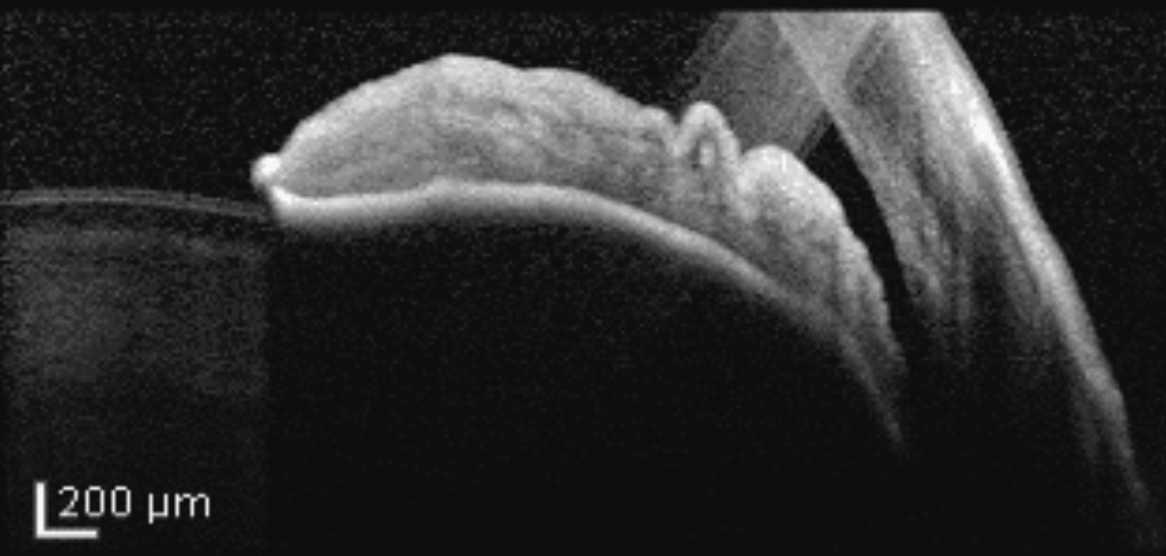

El iris en meseta tendrá un aspecto diferente en la gonioscopia. "En lugar de exhibir una configuración típica de bomba - en la que el iris se ondula hacia adelante y ocluye la pupila en el cierre del ángulo primario - el iris en meseta muestra más una rotación anterior o un desplazamiento anterior del cuerpo ciliar y la raíz del iris", continúa. “En este caso, la raíz del iris se empuja más periféricamente hacia el ángulo debido a las variaciones anatómicas, en comparación con el iris que simplemente se abulta hacia el ángulo".

Muchos oftalmólogos integrales no están familiarizados con las características diagnósticas asociadas con el iris en meseta. En la gonioscopia, los hallazgos específicos que sugieren iris en meseta incluyen "la señal de doble joroba", en la que se puede ver un efecto de ondulación del iris periférico.

En la gonioscopia, el iris bombe es la presentación clásica del cierre angular primario, en que el iris se ondula hacia adelante y ocluye la pupila.Todas las fotos son del Dr. Sanjay Asrani

| El "signo de la doble joroba" sugiere iris en meseta, mostrando un efecto ondulado del iris periférico. La identificación precisa de la configuración del iris en meseta influye en la planificación del tratamiento, dicen los especialistas en glaucoma. |

| El iris en meseta se presenta con una posición anterior anormal del cuerpo ciliar con la raíz del iris empujada más periféricamente hacia el ángulo. |